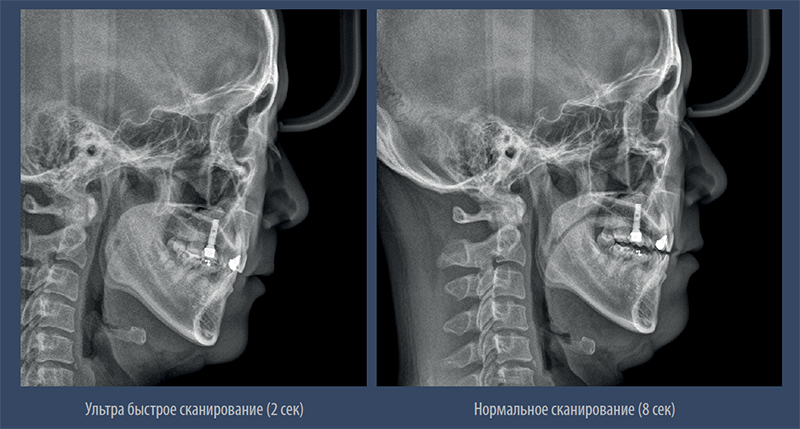

Режим быстрого сканирования.

– Минимальная доза облучения в режиме быстрого сканирования

– Качественное изображение без артефактов движения и искажений

Режим быстрого сканирования.jpg